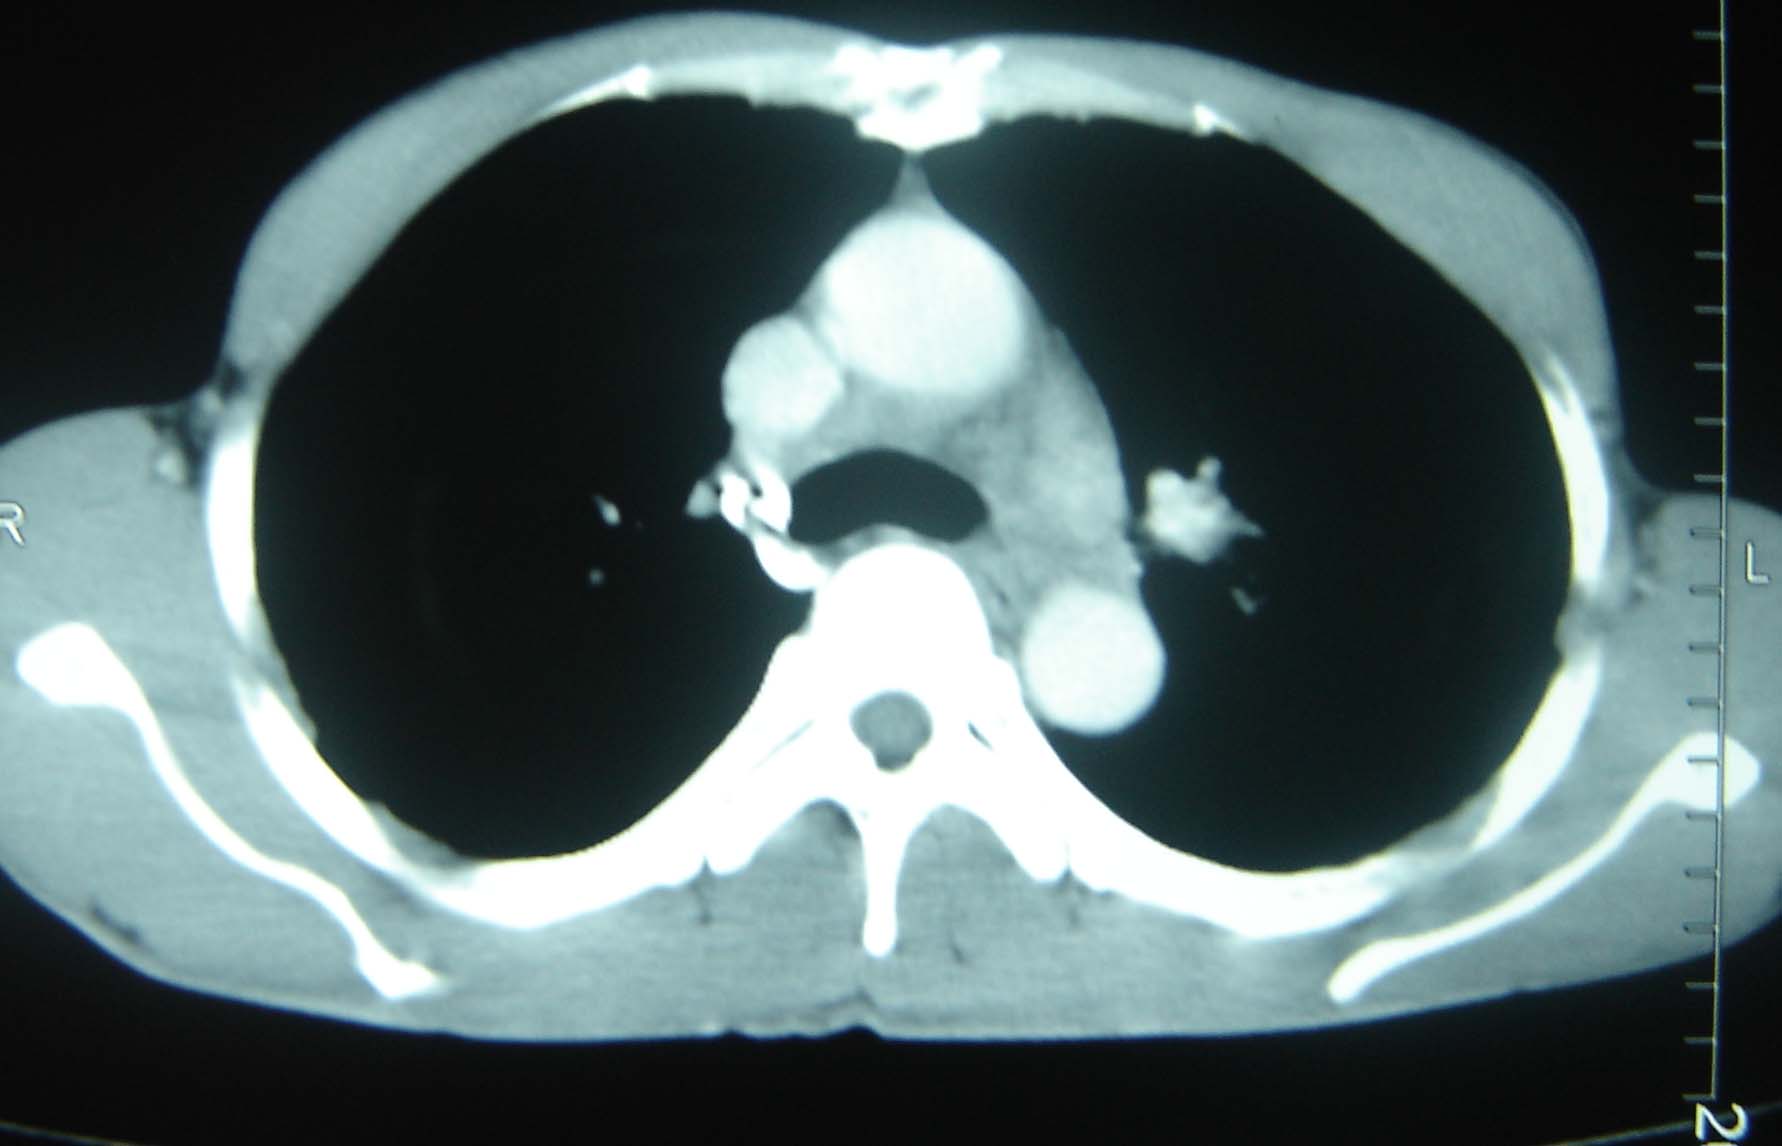

标题: CT25321:两肺多发结节 请会诊 [打印本页]

标题: CT25321:两肺多发结节 请会诊

男 、43岁,咳嗽胸痛,装修工,平时接触粉尘较多,有吸烟史10多年,纤维支气管镜检查未发现异常,胃镜、腹部b超检查亦未发现异常,颈部淋巴结活检未发现肿瘤细胞。